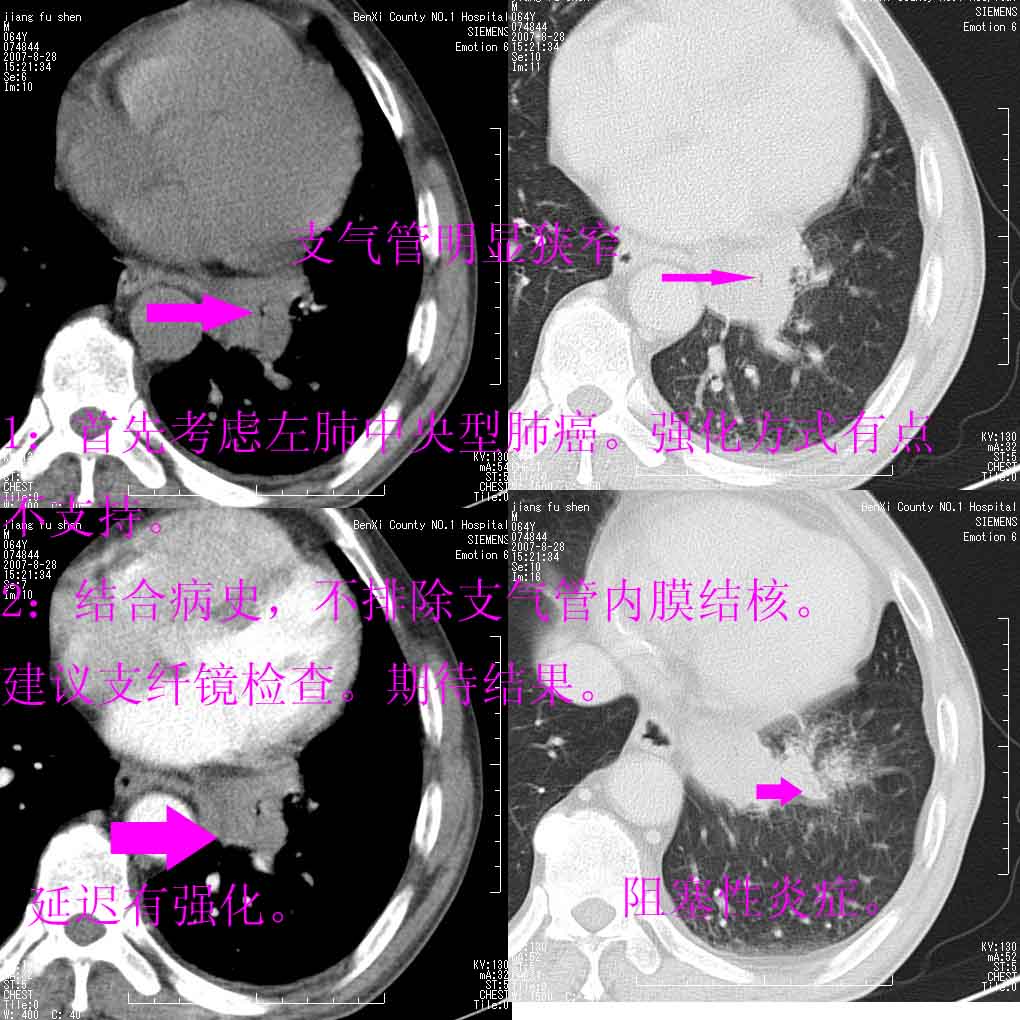

男、64、咳嗽、发烧一周、左肺呼吸音稍弱。既往肺结核,右手结核。

本次扫描患者未带原片,左肺下叶发现病灶。左肺上叶空洞,5组淋巴结肿大,1cm左右。

平扫20-33hu

增强31-33hu

1分半44-52

2分55-67

左肺下叶前内基底段支气管明显偏心性狭窄,周围分叶状肿块,伴有阻塞性肺炎,支持肺癌可能性大。

考虑左肺中央型肺癌并阻塞性肺炎

病灶边缘可见多量较长棘影及纤维条索状影,除外病灶边缘较光整,病灶有分叶表现,但多表现为较浅分叶,且向周围伸出之叶多呈尖角改变,且边缘较光整,病灶增强呈中度延时增强,且早期及中期仅轻度增强,结合患者病史,多考虑继发型肺结核,炎性增殖灶形成,不除外肺癌

支持中心型肺癌,不除外内膜结核。

左下叶支气管变窄,管腔光滑。软组织形状不规侧,分叶呈角形。结合病史考虑结核可能性大。肺癌不除。